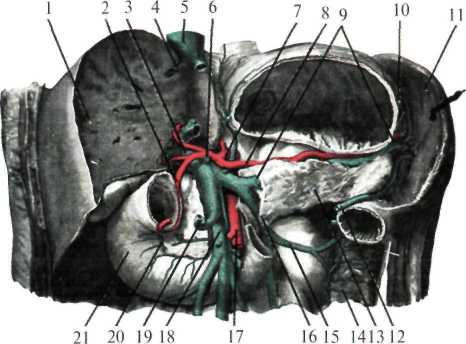

Кровоснабжение. Питает поджелудочную железу верхняя панкреатодуоденальная артерия (ветвь гастродуоденальной артерии из системы чревного ствола), нижняя панкреатодуоденальная артерия из верхней брыжеечной артерии и ветви, отходящие от селезеночной артерии (рис.1.30, 1.31).

Рис. 1.30. Поджелудочная железа (брюшина частично удалена, выделен проток поджелудочной железы, двенадцатиперстная кишка вскрыта).

1 — gl. suprarenalis dextra; 2 — ren dexter; 3 — a. et v. pancreaticoduodenalis superior; 4 — duodenum;

5 — papilla duodeni minor; 6 — ductus pancreaticus accessorius; 7 — ductus choledochus; 8 — papilla duodeni major; 9 — a. et v.pancreaticoduodenalis inferior; 10 — v. mesenterica superior; 11 — a. mesenterica superior et plexus mesentericus superior; 12 — ductus pancreaticus; 13 — ren sinister; 14 — ramus pancreaticus (a. splenica); 15 —splen; 16 —nodi lymphoideipancreaticosplenicum; 17— gl. suprarenalis sinistra; 18 — a. splenica et plexus splenicus; 19 — nodi lymphoidei coeliaci; 20 — truncus coeliacus;

21 — plexus coeliacus; 22 — a. gastroduodenalis; 23 — a. hepatica propria; 24 — v. portae; 25 — ductus choledochus.

К сосудам селезенки относятся селезеночная артерия и вена, проходящие в толще диафрагмально-селезеночной связки (рис.1.31)